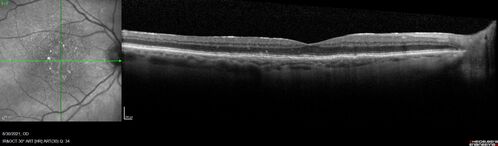

Pigment migration in dry age-related macular degeneration

80 year old female. Dry AMD with GA in the left eye and pigment migration visible on OCT scan.

VA 20/40 OD, 20/160 OS